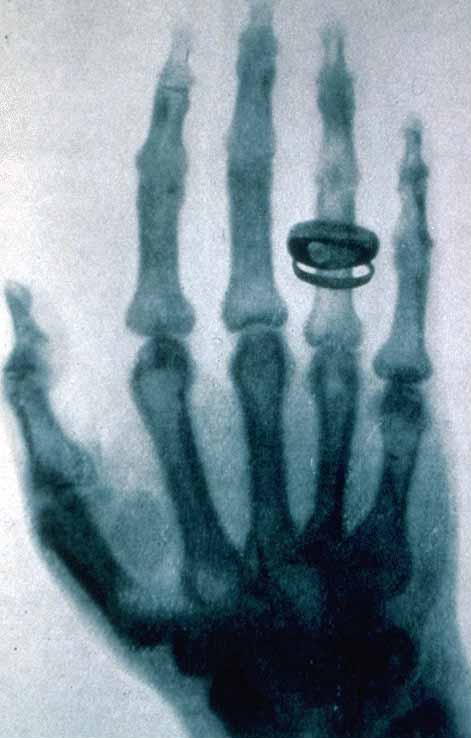

Radiografia mâinii unui prieten şi apoi a mâinii soţiei sale a făcut ca descoperirea razelor X să ajungă un subiect public, întrucât aceste imagini care practic prezentau scheletul mâinii au fost asociate cu moartea şi au hrănit idei cu iz catastrofic. Pe de altă parte, temerea de acest tip de raze era justificată pentru că cercetători care le-au folosit au avut probleme de sănătate.

Imagine a mâinii fiziologului elveţian Albert Kölliker realizată în 1896 în timpul unei conferinţe